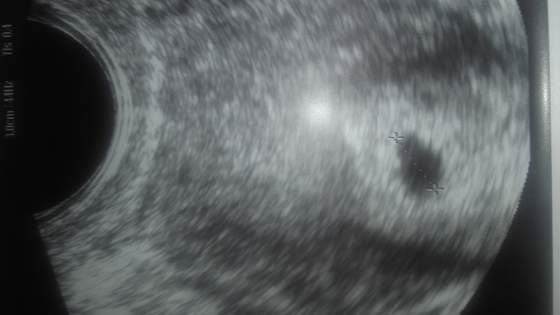

Estriadol mam trochę ponad 5500 j., prg 2,5 j. ( i już myślałam, że to przekreśla możliwość podania świeżego zarodka - a w Novum robią transfery do prg 3,5 j., więc mam jeszcze szansę). Pęcherzyków mam ok 10 (11-12 mm, pogubiłam się w liczeniu, jak ona wymieniała) + ok 15 mniejszych.

Endometrium 10 mm (też ładne).